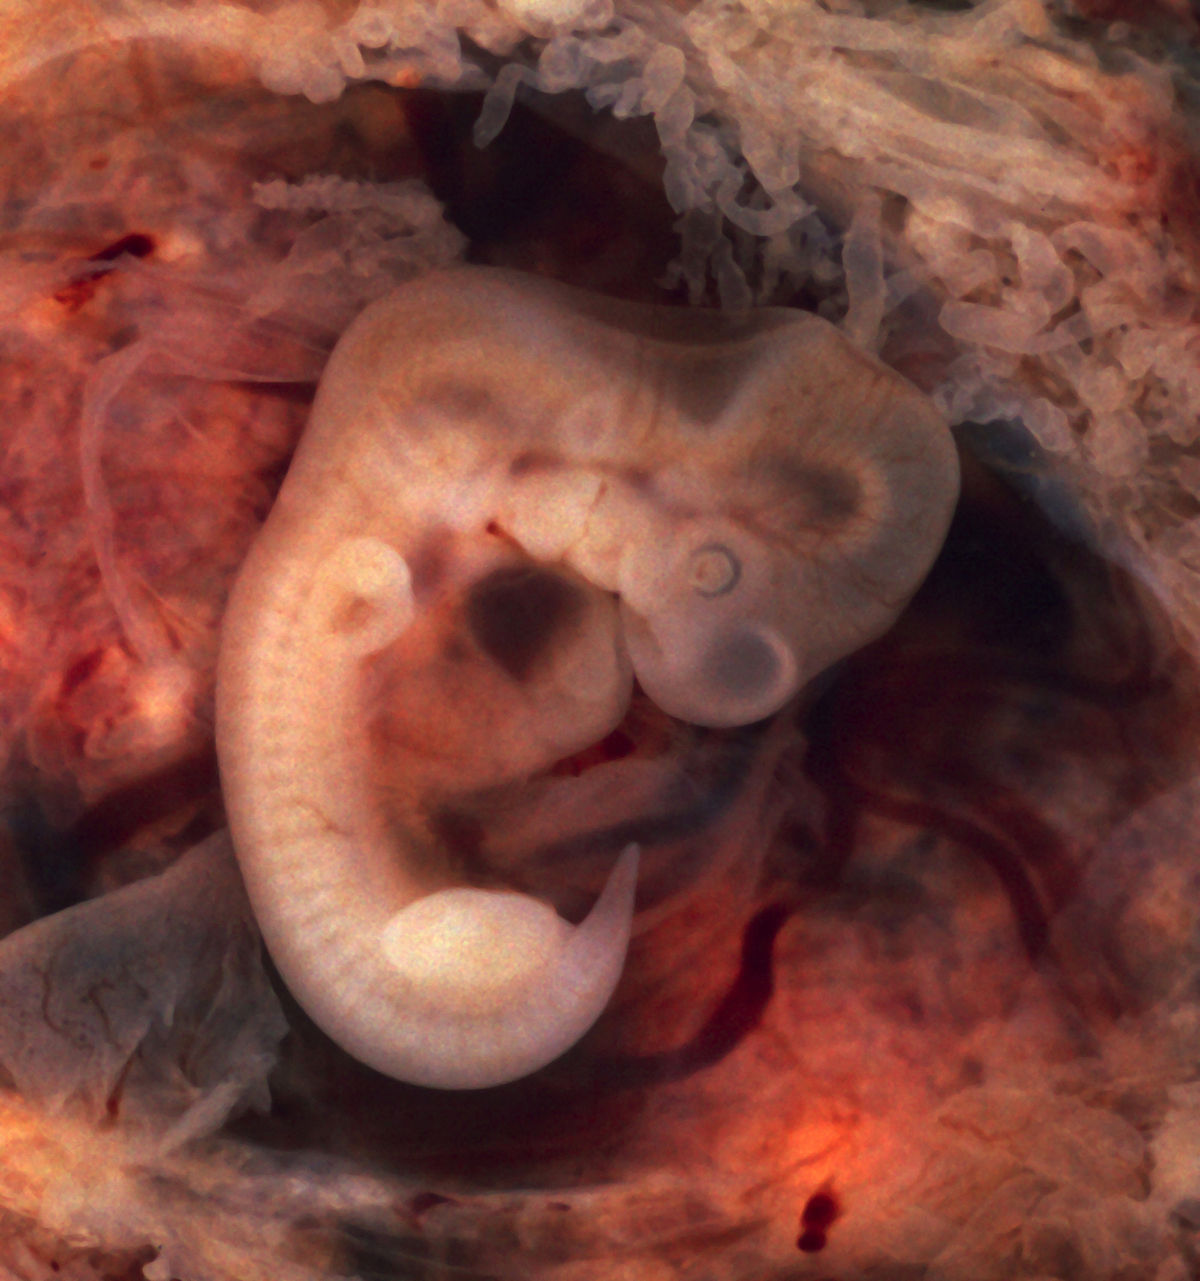

Развитие эмбриона: Что происходит на 3 неделе беременности

Раздел: Фотопанорама